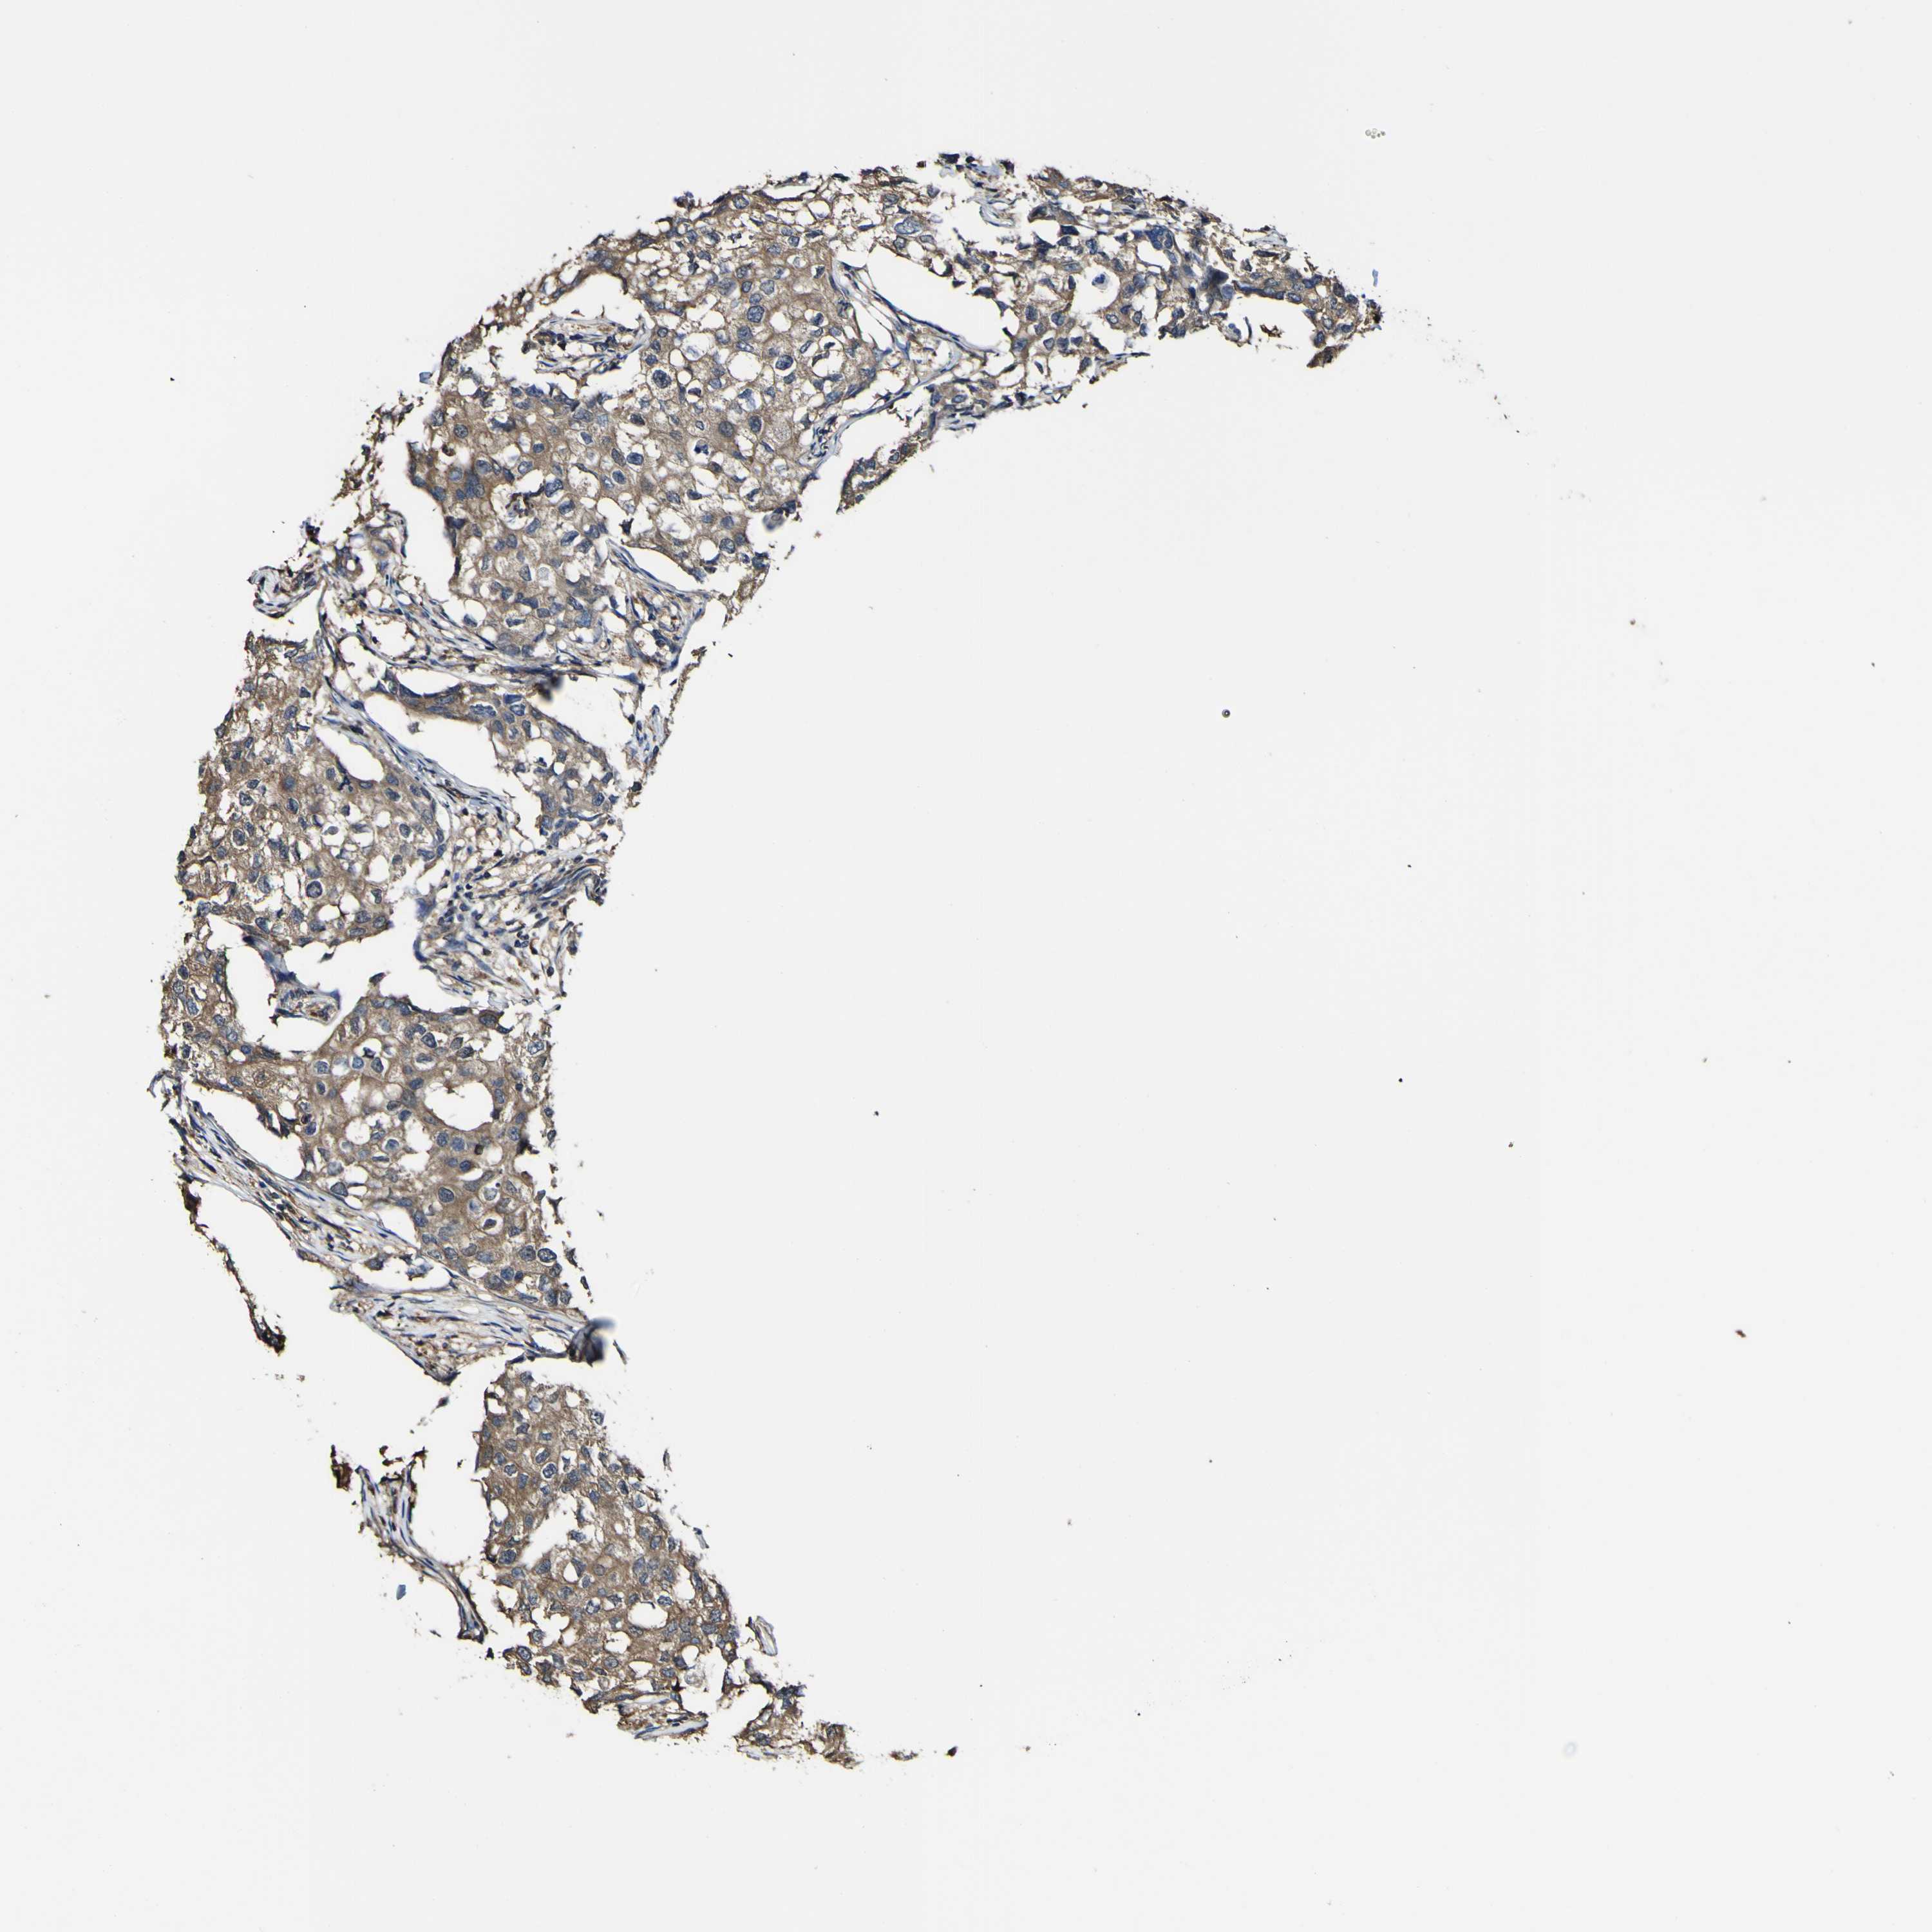

CANCER BREAST CANCER Show tissue menu

BRCA TCGA BRCA VALIDATION PROTEIN EXPRESSION